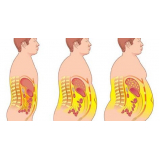

Há momentos em que é necessário ter por perto profissionais qualificados e dedicados à pronta recuperação do paciente. A FF Cirurgia Plástica oferece e coloca à sua disposição o que existe de mais atualizado em procedimento cirúrgico para abdominoplastia com lipo. Com o objetivo de levar qualidade à vida dos clientes, a instituição oferece infraestrutura adequada às necessidades de cada um: cuidado médico humanizado, realizado através de dedicação, profissionalismo e amor.